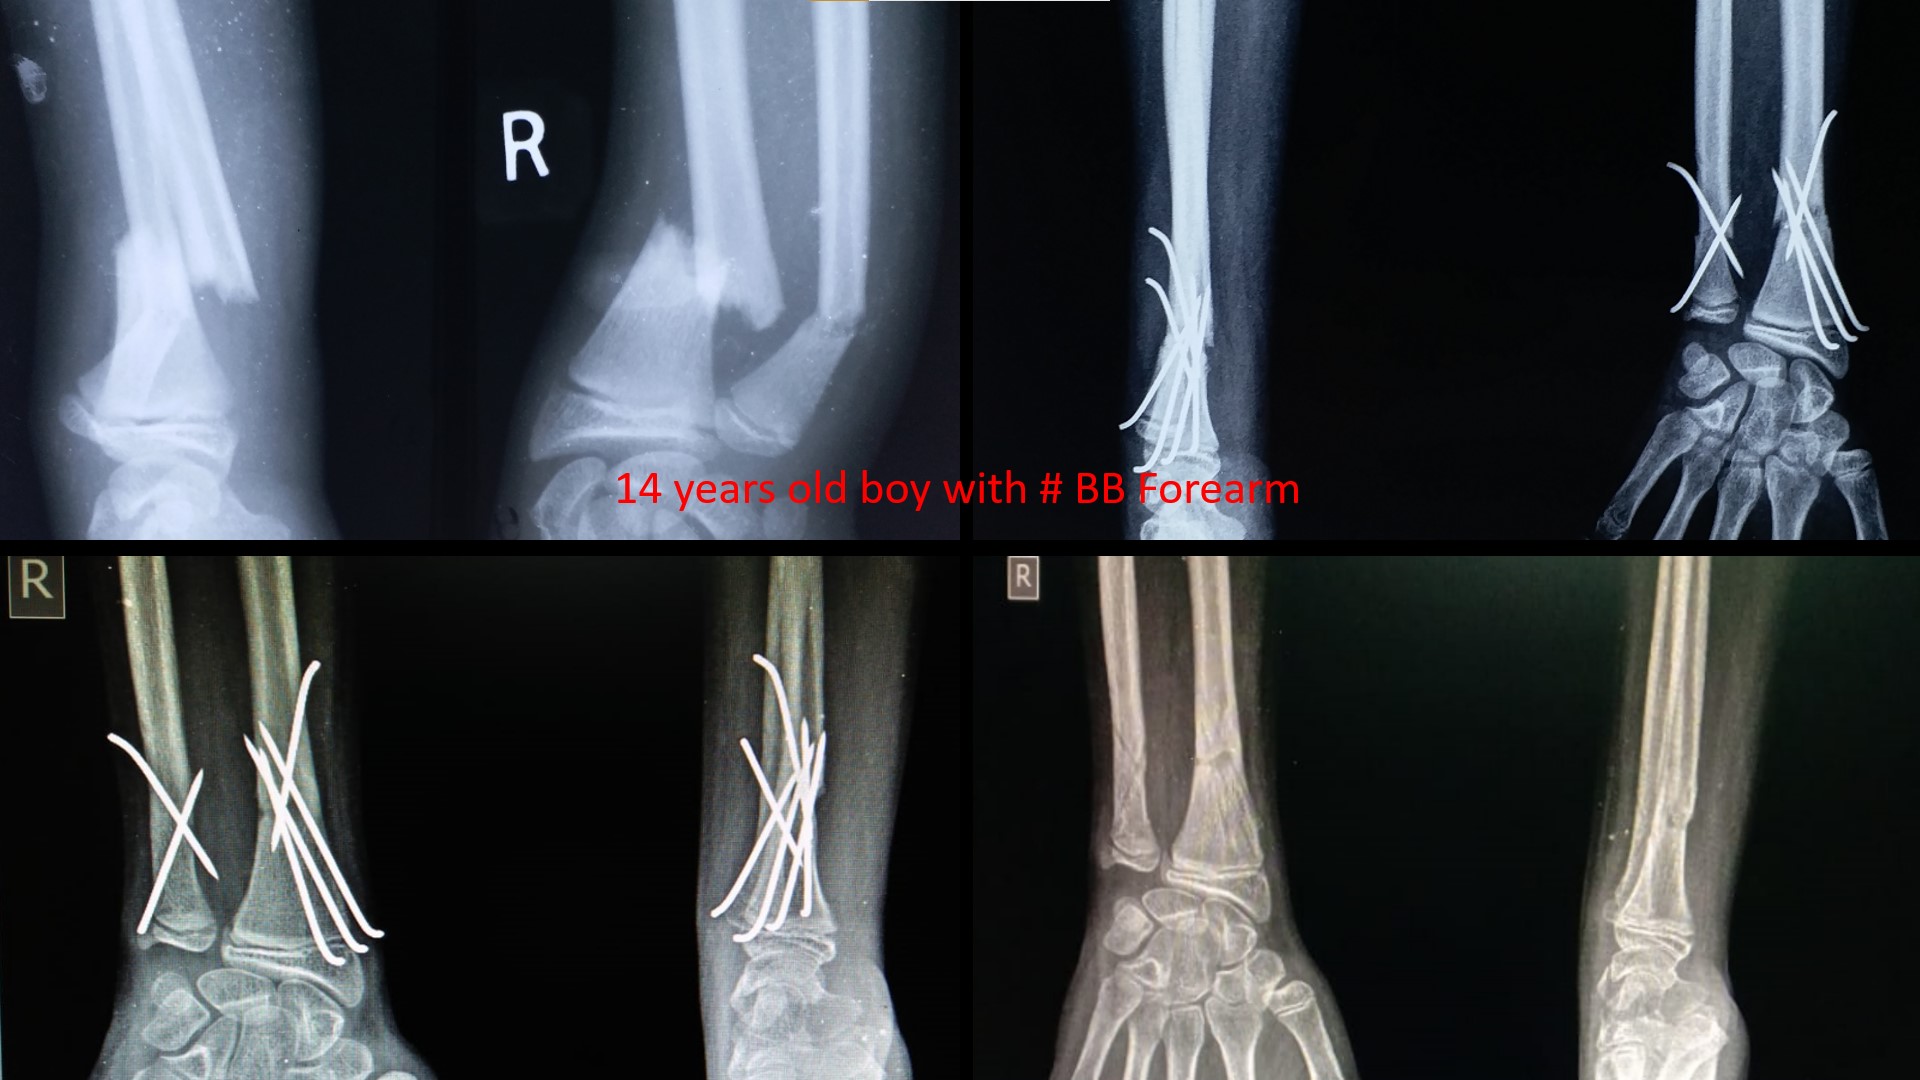

FRACTURE LOWER 3RD FOREARM